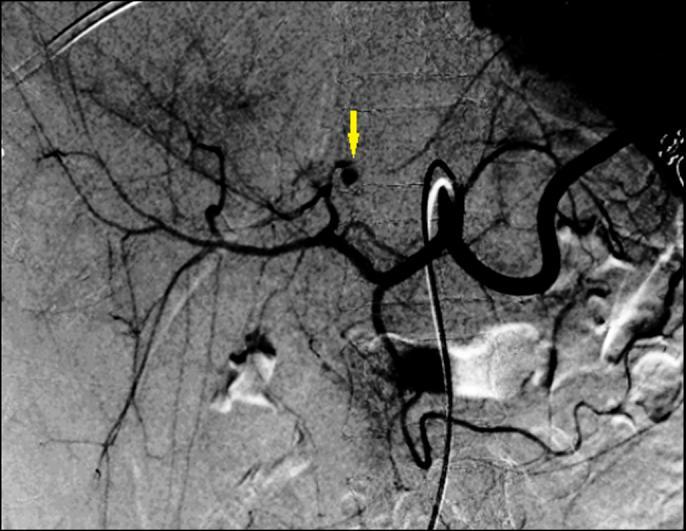

Hepatic artery pseudoaneurysm (HAP) commonly occurs after trauma and is rarely seen as a complication of pyogenic liver abscess. Patients with HAP can present with hemobilia secondary to arterobiliary fistula. We report a case of a 29-year-old woman who presented with abdominal pain, fever, and jaundice, who was diagnosed to have a pyogenic liver abscess that had led to the development of left HAP, presenting with hemobilia. The patient was successfully managed with endovascular coil embolization.

肝动脉假性动脉瘤(HAP)常见于外伤后,作为化脓性肝脓肿的并发症则较为罕见。HAP患者可因动脉胆管瘘出现胆道出血。我们报告一例29岁女性患者,她因腹痛、发热和黄疸就诊,被诊断为化脓性肝脓肿并发左肝HAP并伴有胆道出血。该患者通过血管内弹簧圈栓塞治疗成功治愈。